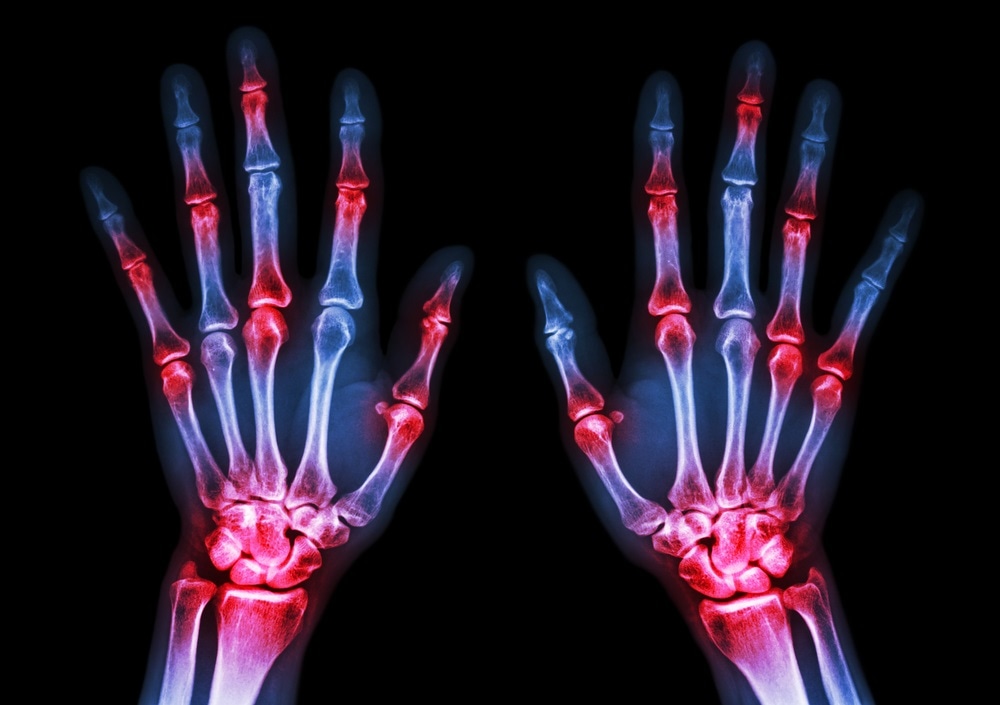

rheumatoid arthritisImage Credit: Puwadol Jaturawutthichai / Shutterstock.com

Arthritis refers to a group of more than 100 chronic diseases characterized by inflammation in the joints that can eventually lead to irreparable damage and debilitating pain and stiffness. Rheumatoid arthritis is an autoimmune form of the disease, where immune cells mistakenly target tissue that lines the joints, causing pain, swelling, and stiffness. Over time, this can damage the joints, cartilage, and surrounding bone.